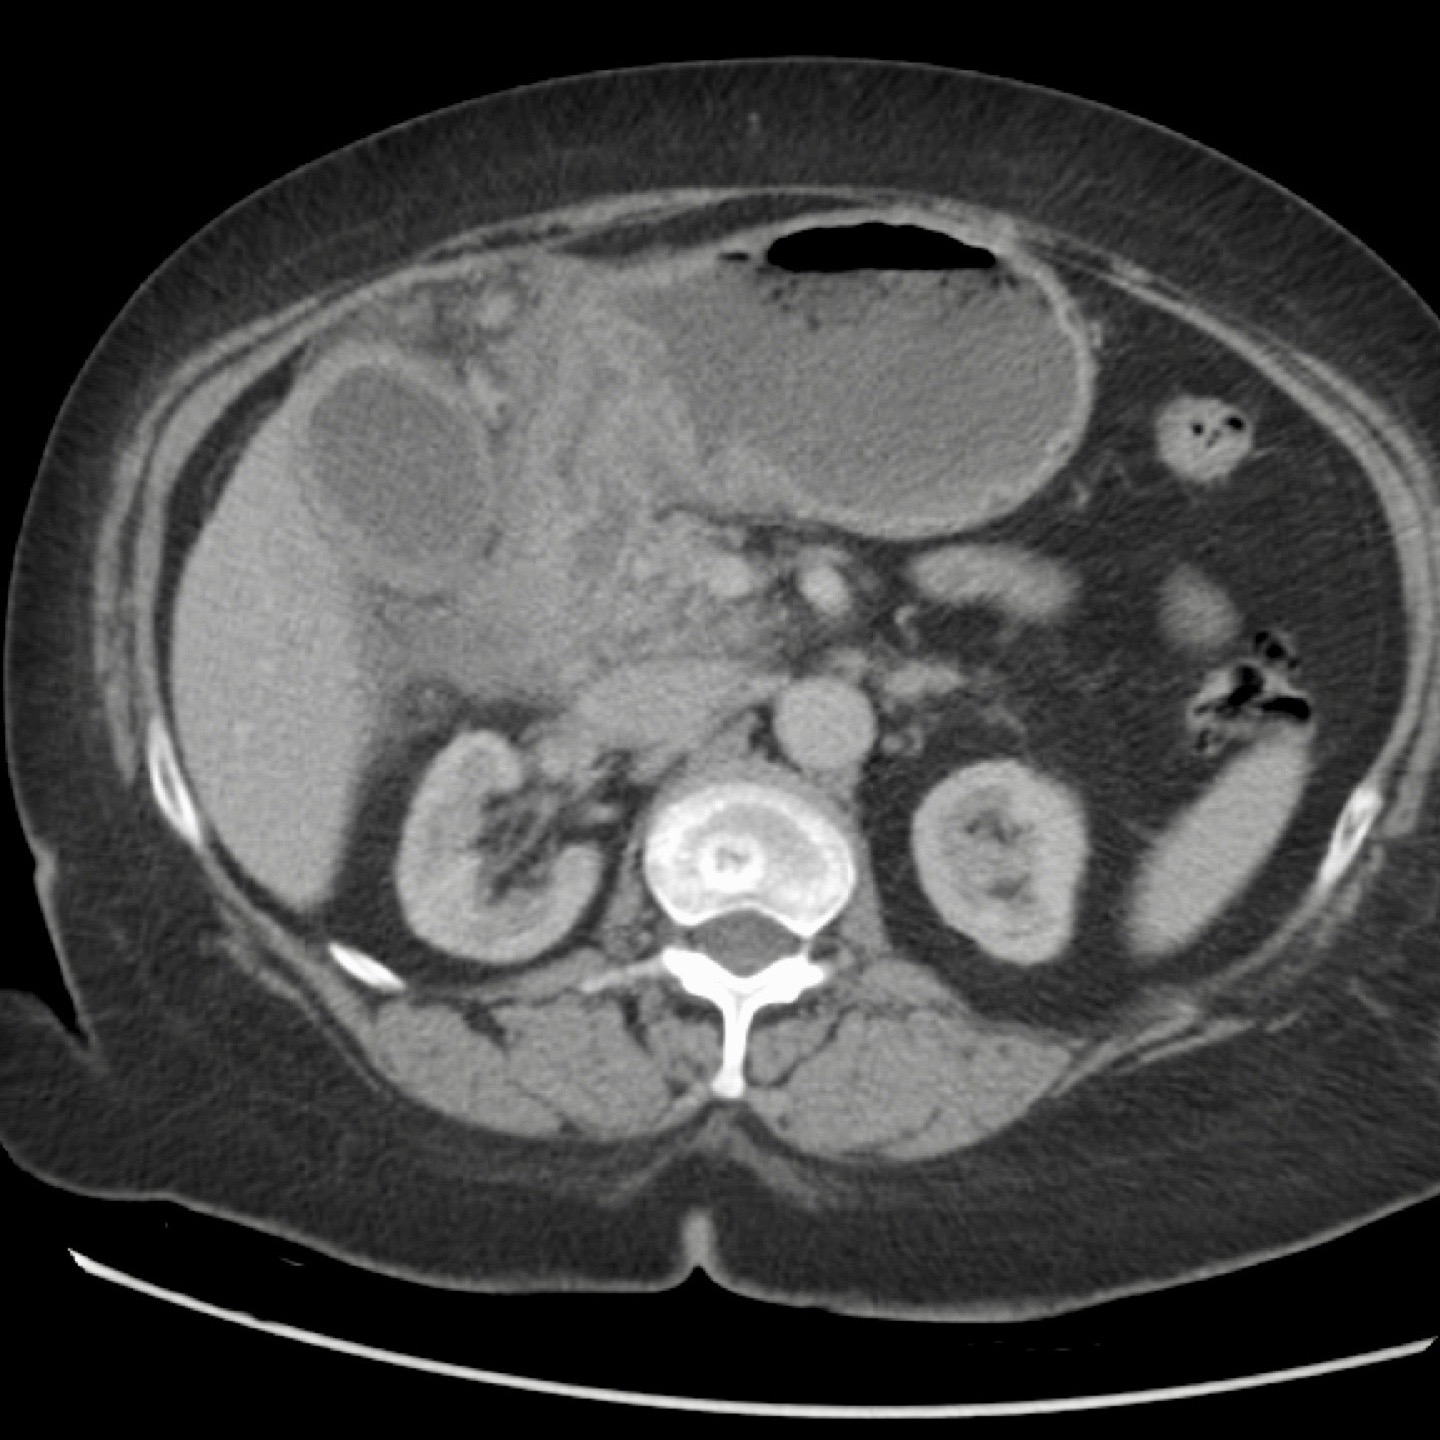

CT trong viêm túi mật cấp

CT có thể rất hữu ích trong các trường hợp siêu âm không cho kết quả chẩn đoán.

Đây là hình ảnh của một bệnh nhân béo phì với đau hạ sườn phải cấp tính trong 6 giờ. CRP 2.

Siêu âm cho thấy túi mật lớn có bùn mật, không quan sát thấy sỏi.

Việc ấn vào túi mật không đáng tin cậy do vị trí cao dưới cung sườn phải.

Không có bất thường siêu âm nào khác.

CT thực hiện cùng ngày cho thấy túi mật lớn với chỉ những thay đổi quanh túi mật kín đáo và không có nguyên nhân nào khác giải thích cho các triệu chứng.

Ngày hôm sau CRP là 105 và CT không tiêm thuốc cản quang lặp lại cho thấy quầng mờ xung quanh túi mật.

Phẫu thuật tiếp theo xác nhận viêm túi mật cấp giai đoạn sớm do sỏi nhỏ trong ống túi mật.